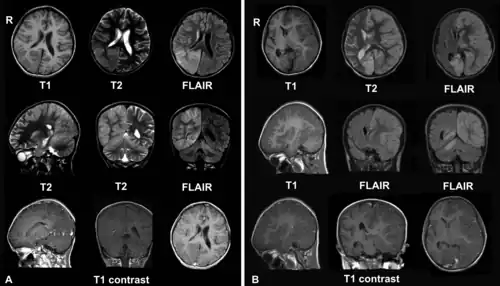

A. Декабрь 2008. У больной была головная боль и epilepsia partialis continua. Обратите внимание на очаги с фокальным отеком мозга в правой теменной и затылочной долях и правом полушарии мозжечка.

B. Апрель 2009. Та же больная, которая теперь в коме с epilepsia partialis continua. Отмечается прогрессирование энцефалита с вовлечением левого полушария мозга и значительным отеком мозга и смещением срединных структур.